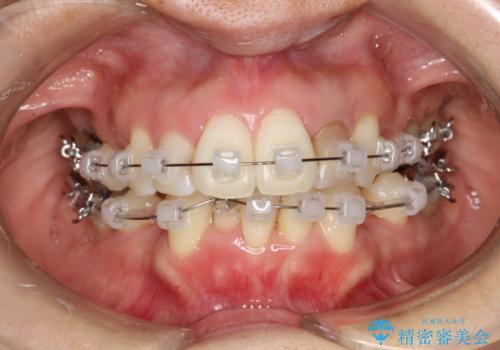

重度のガタガタと出っ歯をワイヤーによる抜歯矯正で整った歯並びへ

- 全体的ながたがたを主訴に来院されました。

上顎の前歯は前方に傾斜して、下顎の前歯は強いガタガタが見られました。

前から4番目の歯を上下左右合計2本抜歯して、歯並びを整える計画としました。

ワイヤー矯正にて治療しました。